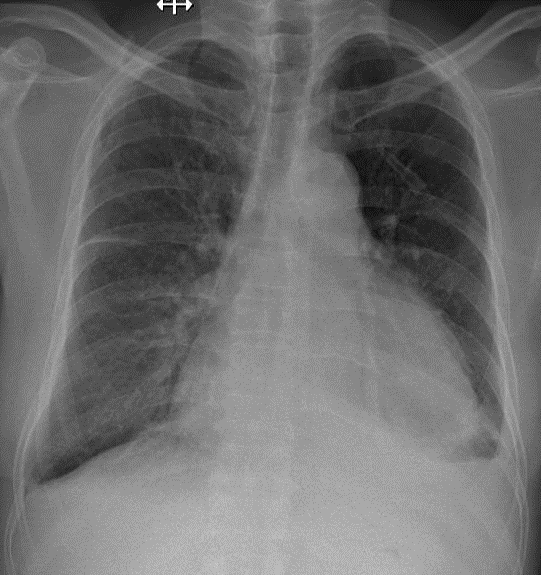

1-Thâm nhiểm phế nang lan tỏa thùy dưới hai phổi -> Viêm phổi 2-Tràn dịch màng phổi (P-T) lượng ít 3-Dày dính màng phổi (P) 4-Tim to